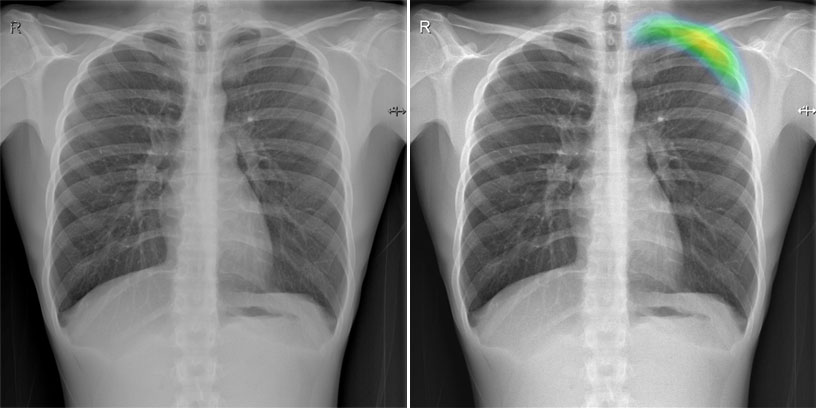

Lunit Inc、Lunit INSIGHT CXR 採用 Lunit 尖端深度學習技術開發,並可偵測 10 項放射線學病徵;

肺塌陷症、鈣化、心臟腫大、實質化、纖維化、縱膈腔擴張、結節、肋膜積液、腹內積氣、氣胸

早期發現和治療潛伏性氣胸非常重要,因為它可能發展到危及生命病況的張力性氣胸。張力性氣胸可導致患有隱匿氣胸的患者需接受侵入性治療。